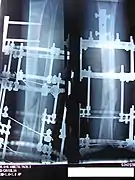

Images

The following case study illustrates the Ilizarov apparatus treatment procedure for a fractured limb. The photographs are of the same patient during the course of treatment.

X-Ray of the fracture site immediately following the application of the Ilizarov method

X-Ray of the fracture site, part 1 (two months following fracture)

X-Ray of the fracture site, part 2 (two months following fracture)

X-Ray of the fracture site (three months following fracture). Note formation of bone callus around fracture site.

X-Ray of the fracture site, part 2 (three months following fracture). Note formation of bone callus around fracture site.

X-Ray of the fracture site, part 2 (four months following fracture)